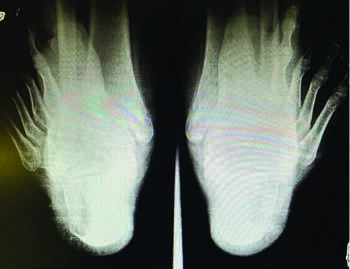

Next, it is critical to perform an appropriate radiographic evaluation, and to do so bilaterally. Assessing the growth plates with a unilateral film and no contralateral comparison may lead to misdiagnosis. Avulsion fracture in untreated Sever’s is a possibility.12 Rachel and team also reported abnormal radiographic findings in 5.1 percent of children with Sever’s leading to more aggressive treatment.13 They felt that without taking images, clinicians could miss lesions requiring more advanced treatment. Taking weight-bearing lateral images allows for evaluation of the calcaneus and a comparison of the two posterior growth plates for continuity and for advancement of closure. Evaluating for bone density, secondary ossification center, and fragmentation are also important.14 One should assess the widths of the growth plates should for possible increased separation or asymmetry, and the use of measuring options, now found on most computer radiography programs, can be helpful.

A dorsoplantar radiographic view can help determine foot type and position, especially at the talonavicular joint. I also utilize a calcaneal axial view with my pediatric patients, and due to their smaller stature, assessment of the hindfoot alignment is possible in this view as well. It is important to remember when treating the pediatric patient that you are treating not just the child, but the parents as well, and performing an X-ray does allow for additional peace of mind for the family.